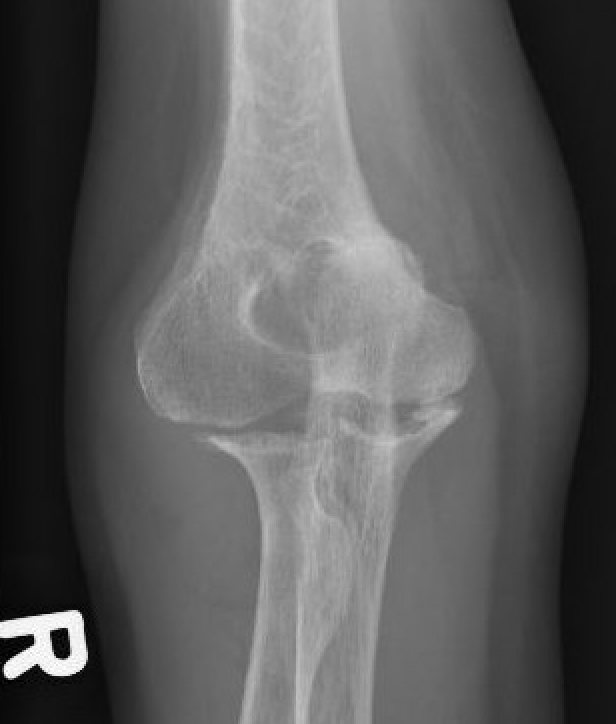

Xray

Articular destruction/ cysts / osteopenia /structural bone loss